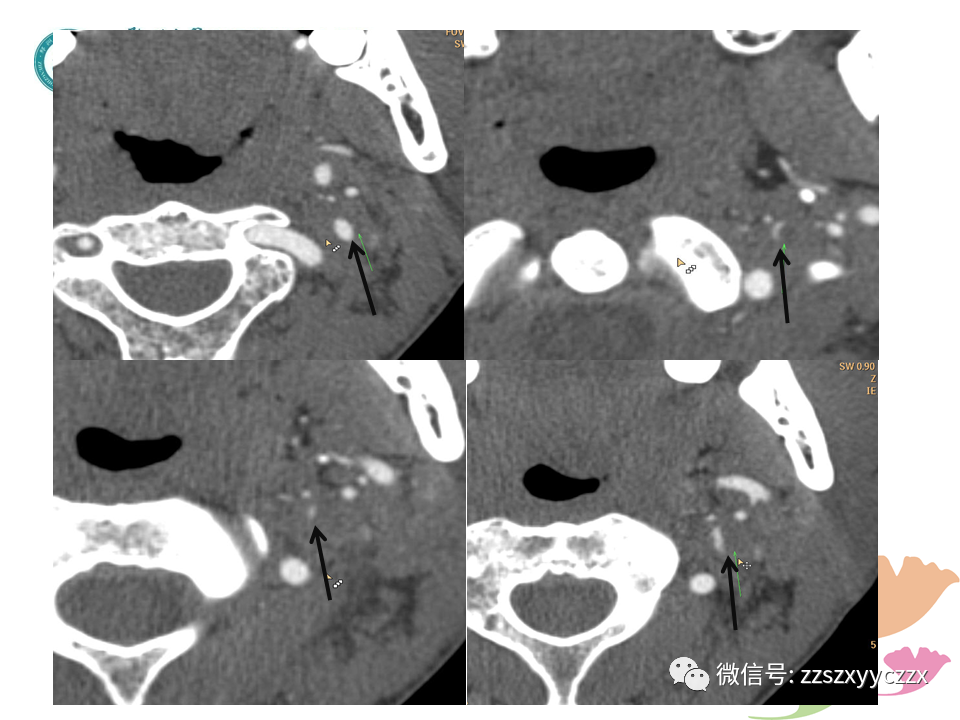

按摩、外伤及不良姿势等是CAD常见原因;本文通过3个病例阐述了颈动脉夹层的超声诊断,也对1例主动脉缩窄的超声学、CTA进行了描述,和大家分享。